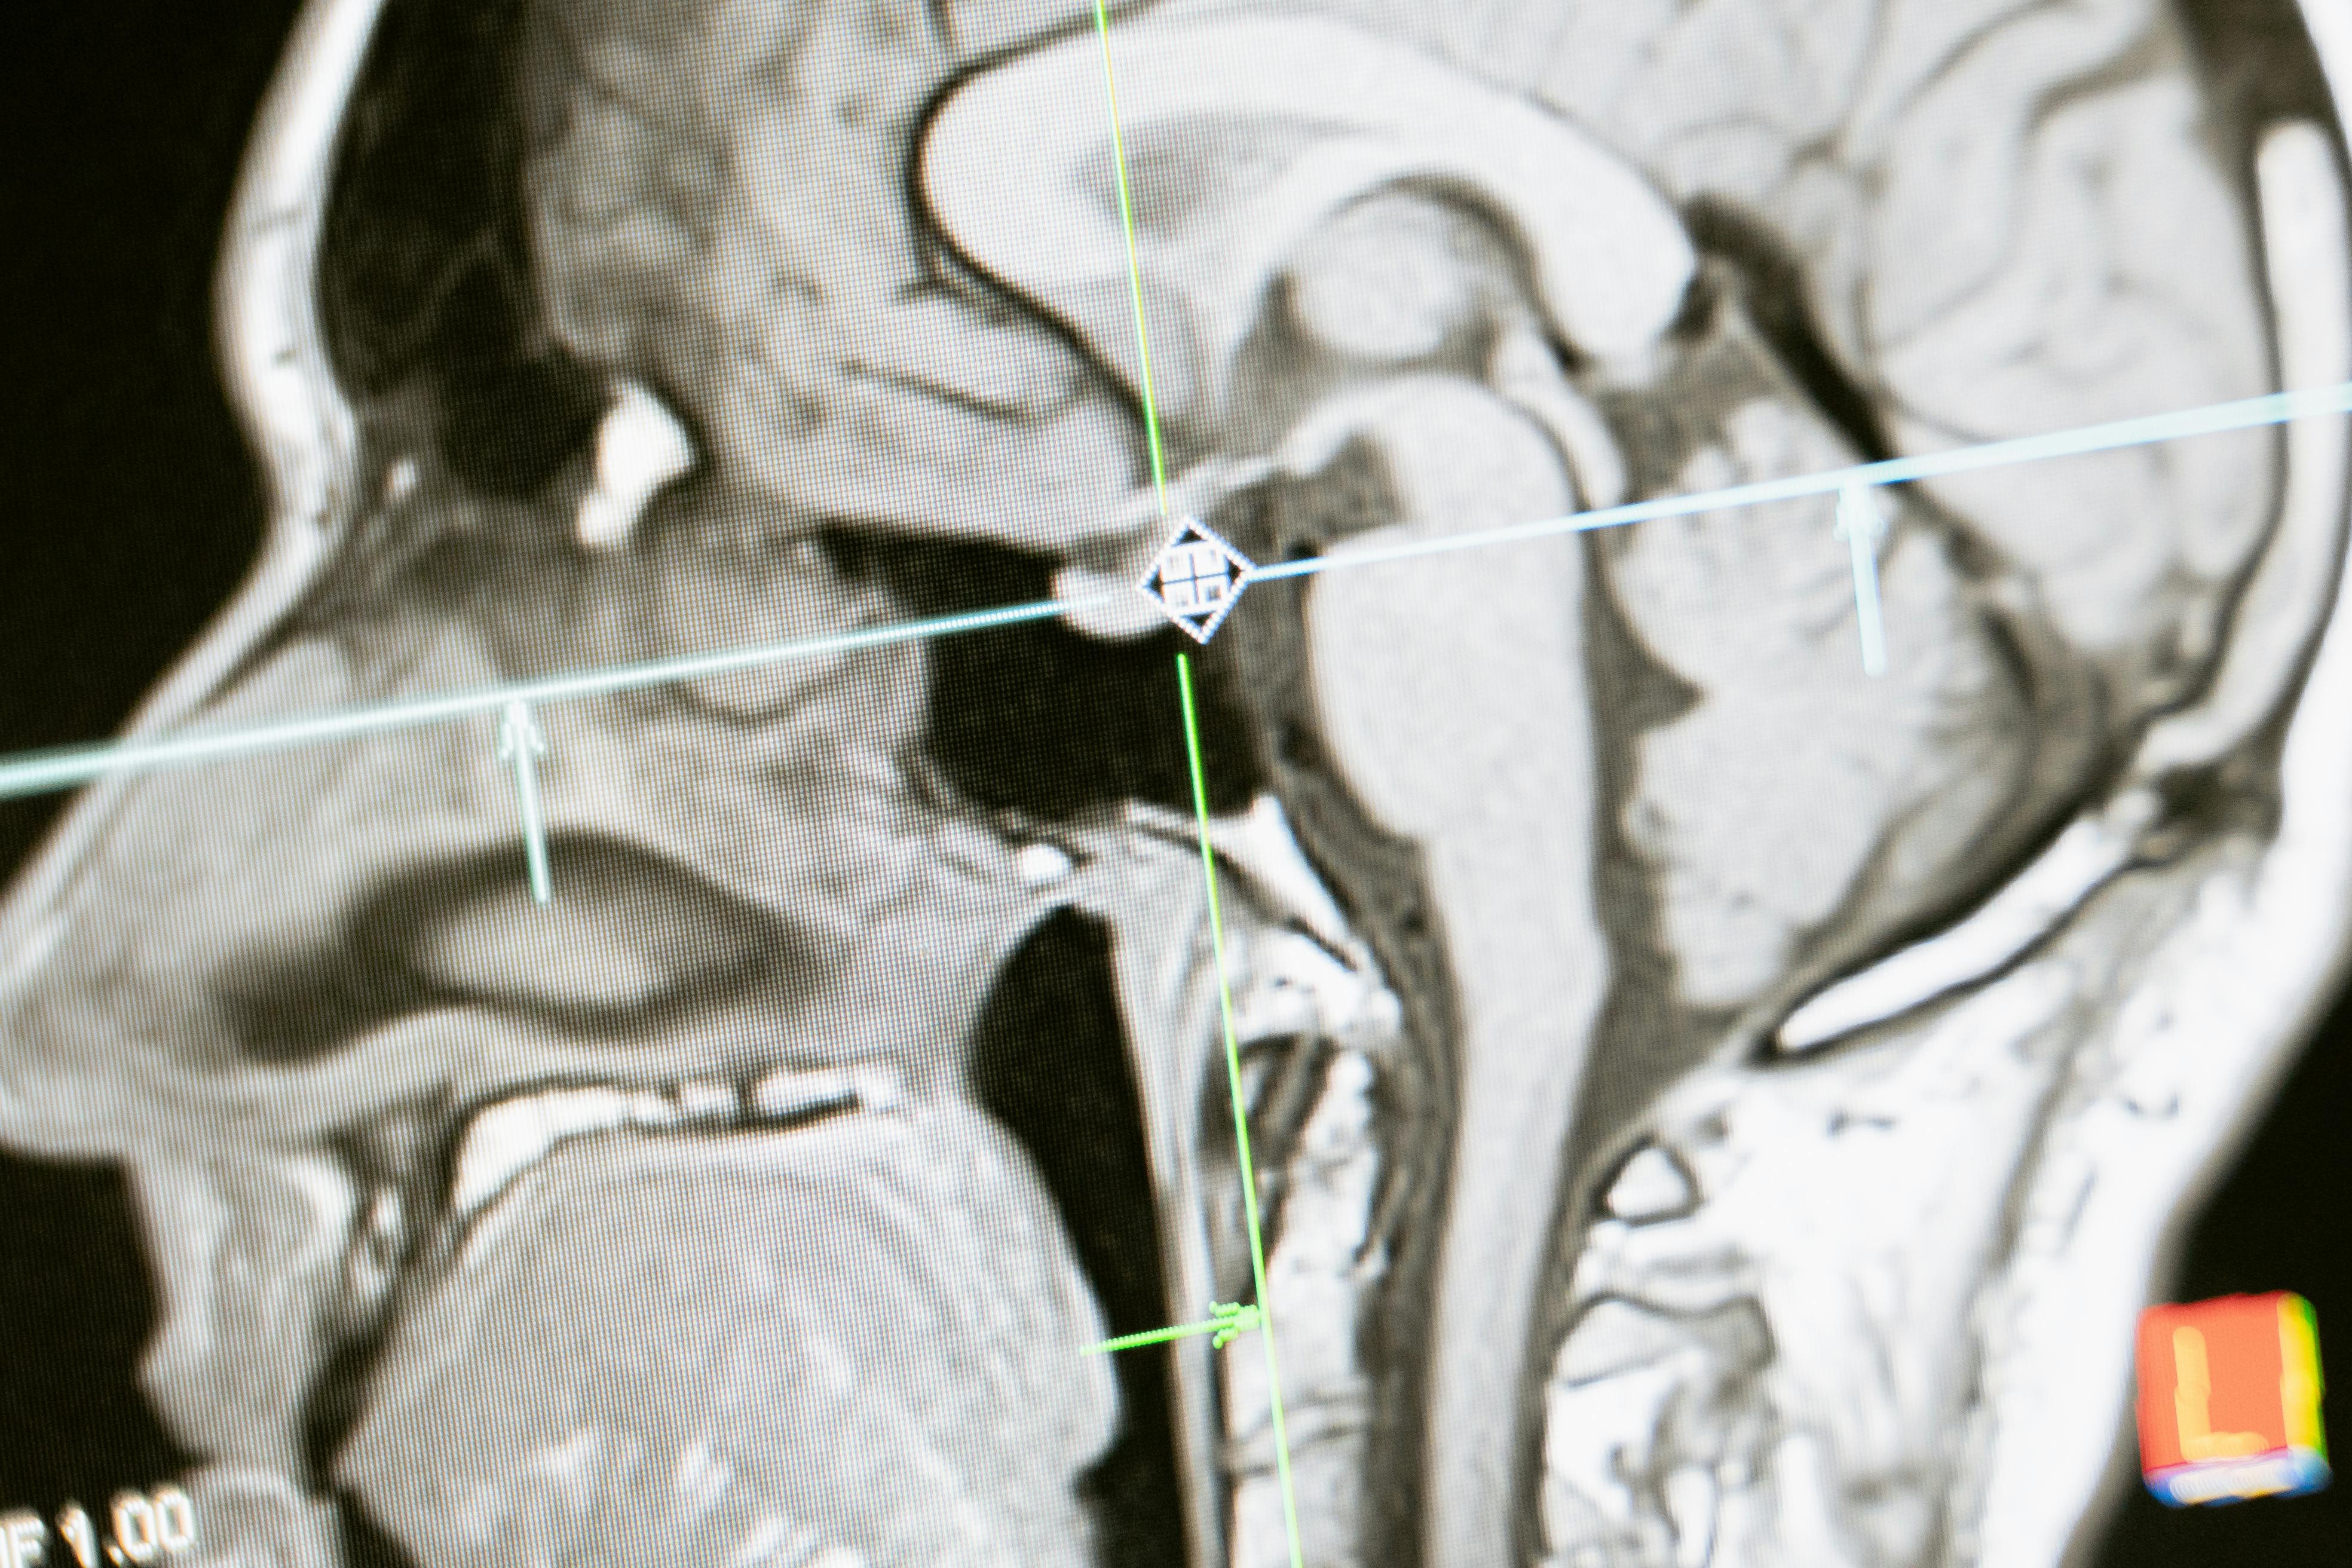

Our FDA-cleared MRI/DTI post-processing viewer enables us to locate the precise areas of the brain affected by injury or disease.

By establishing the exact location of the injury, we can draw connections between affected brain areas and potential cognitive or behavioral deficits.